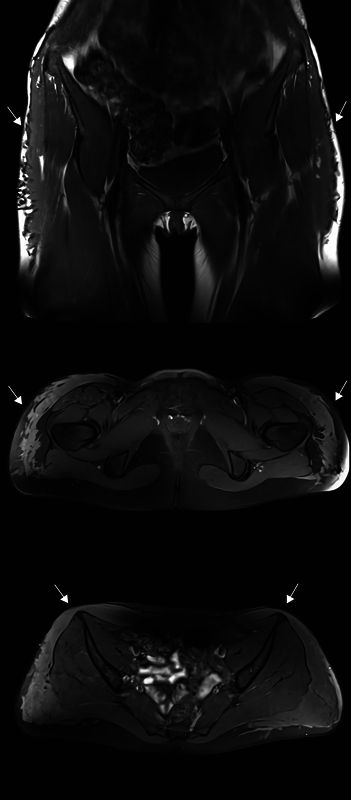

臀部填充注射作为一种整容手术正变得越来越流行,这导致了预期并发症数量的增加,强调了报告已知的、严重的和以前未发现的并发症的重要性,以及它们可能的治疗策略。我们报告了一位18岁的女性,她在注射填充剂进行丰臀手术后出现了严重的长期并发症,包括填充剂移位、感染导致感染性休克和非甲状旁腺高钙血症,这可能导致肾功能不全。到目前为止,我们还没有发现任何描述非甲状旁腺高钙血症与充水之间关系的报告。此外,我们概述了一种涉及微创方法的治疗方案,包括每日冲洗,手动按压和被动抽吸。在随访中,患者恢复了日常生活,除了右大腿内侧有一个实性肿块外,没有持久的后遗症。

Filler injections for buttock augmentation are becoming more popular as a cosmetic procedure, which leads to an expected increase in the number of complications emphasizing the importance of reporting cases with both well-known, severe, and previously undiscovered complications, as well as their possible treatment strategies. We present an 18-year-old woman who suffered severe long-term complications following Aquafilling injections for buttock augmentation, including filler migration, infection leading to septic shock, and nonparathyroid hypercalcemia, which has the potential to cause renal insufficiency. To date, we have not found any reports describing the association between nonparathyroid hypercalcemia and Aquafilling. Additionally, we outline a treatment regimen involving a minimally invasive approach, which includes daily irrigation, manual compression, and passive evacuation. At follow-up, the patient returned to her everyday life with no lasting sequelae, except for a solid mass medially on the right thigh.